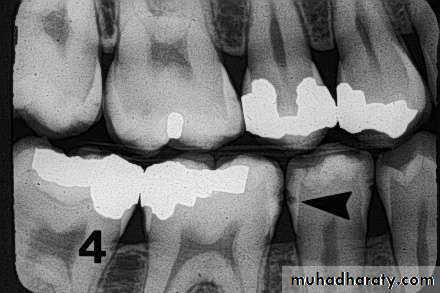

Recurrent cariesIt is diagnosed whenever there is softness due

to caries at a defective margin, and when the tip

of a periodontal probe can enter the defect

without any resistance.

A restoration with a discolored margin or a small

marginal ditch (<0.5 mm or the head of the

probe) is recorded as an early recurrent

carious area. A larger defect should be

classified as advanced recurrent carious area

There are two valid indicators of recurrent (secondary) caries:

• softness at the margin of a filling that is detectedusing an explorer or

• presence of a large defect (a minimum diameter of

0.4 mm) at a margin of a filling with softness in the

area.

Large defects are associated with a high level of colonization with cariogenic bacteria.

Marginal discoloration by itself is not a valid sign for

dental caries.